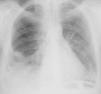

Caso clínicoCaso clínico n.° 1Doente do sexo feminino com 39 anos, sem antecedentes patológicos conhecidos e sem medicação habitual. Recorreu ao serviço de urgência (SU) por quadro com cerca de uma semana de evolução de lombalgia direita e dispneia progressiva para esforços moderados, não referindo febre, tosse ou expetoração. Apresentava-se normotensa com taquiarritmia e ligeira insuficiência respiratória hipoxémica. Analiticamente com padrão inflamatório/infecioso, ECG com taquiarritmia por fibrilhação auricular com resposta rápida (+/-115bpm) e radiografia de tórax com índice cardiotorácico aumentado e infiltrado segmentar no terço médio do hemitórax direito (Figura 1).